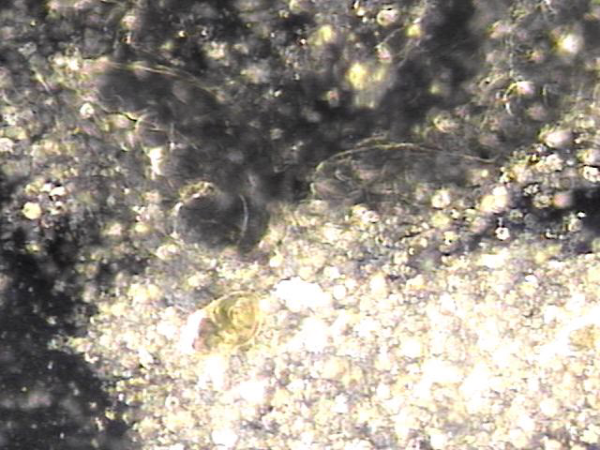

내원 당일 전립선의 표적 치료후 배출된 전립선액의 배양과 PCR 검사를 한후 현미경학적 검사상 치료된 사정관 결석과 전립선의 결석 자료입니다.

On the day of the visit, following targeted prostate treatment, prostatic fluid was discharged and analyzed through culture and PCR testing. Microscopic examination revealed treated ejaculatory duct stones and prostatic calculi.